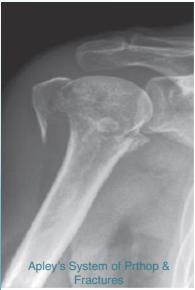

Common Fracture Sites ✓

- Proximal humerus